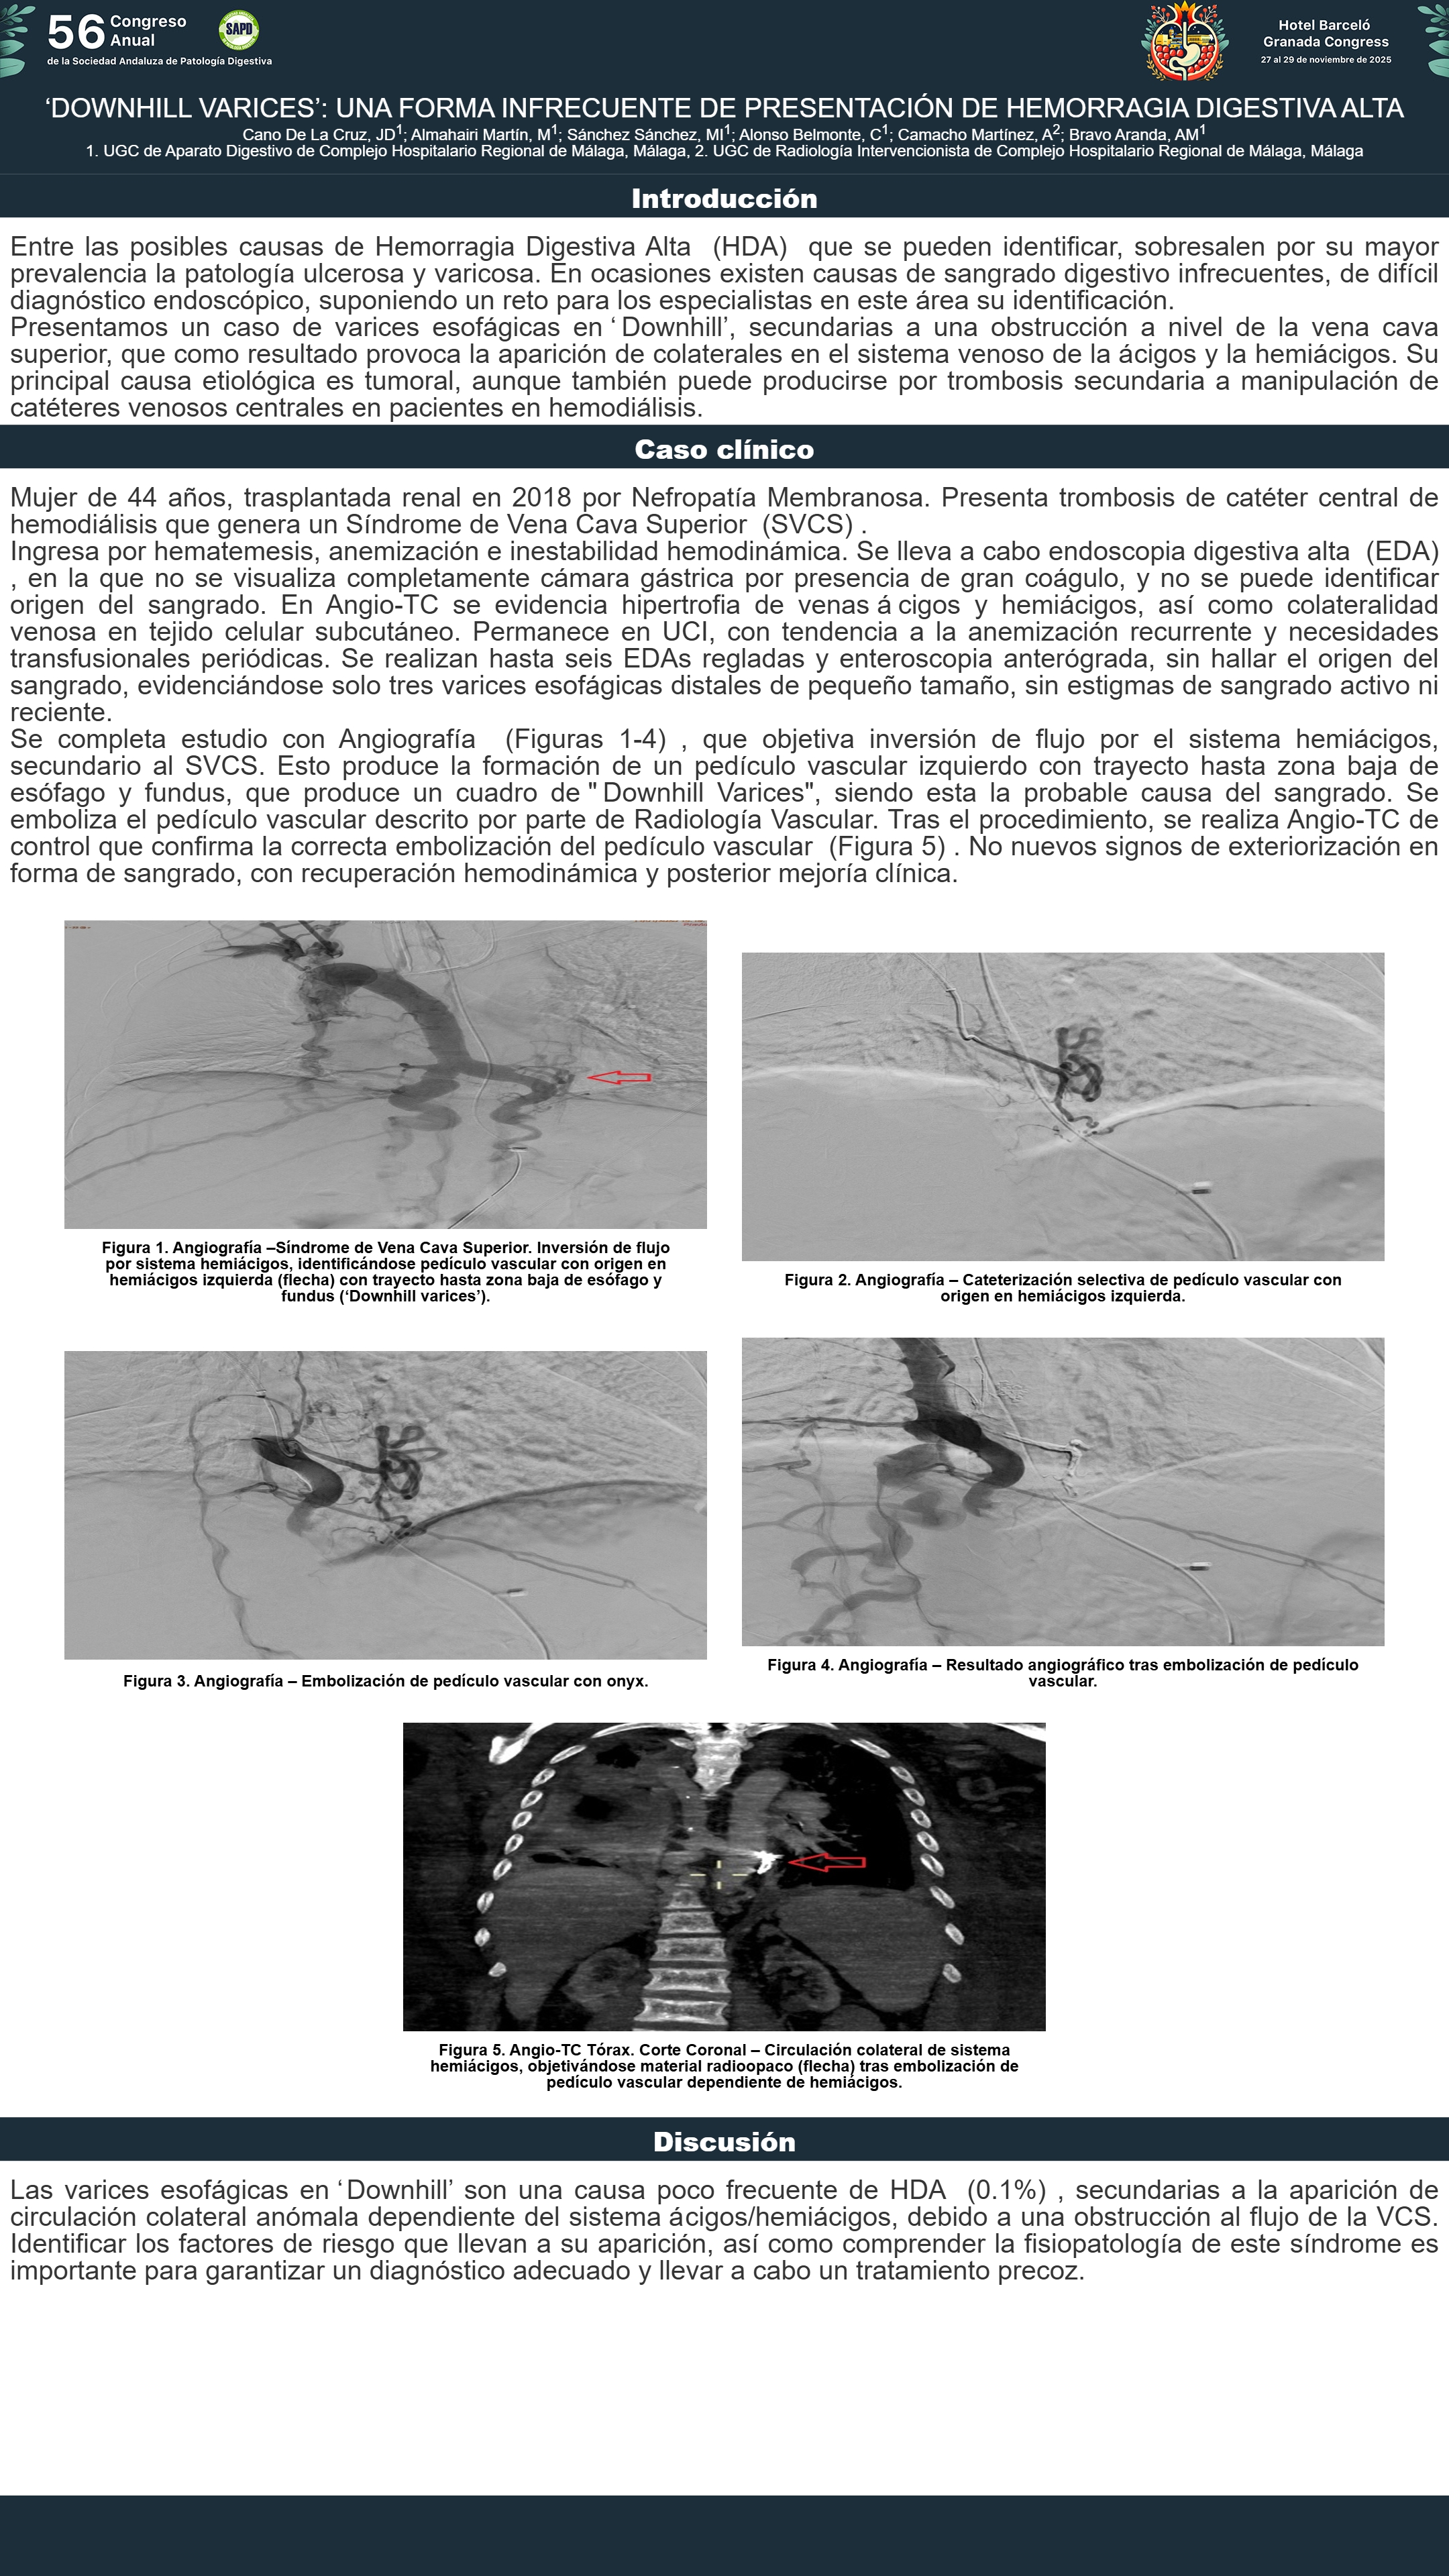

[CP-167] ‘DOWNHILL VARICES’: UNA FORMA INFRECUENTE DE PRESENTACIÓN DE HEMORRAGIA DIGESTIVA ALTA